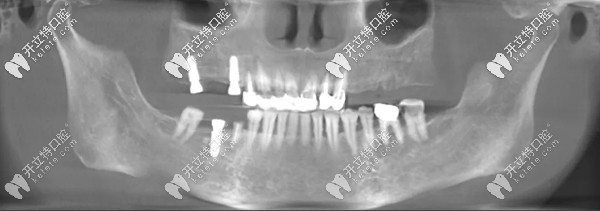

王阿姨多顆牙缺失(右下1顆、右上2顆),她說(shuō)之前牙齒做過(guò)治療后就出現(xiàn)掉牙現(xiàn)象,每次咀嚼稍微堅(jiān)硬的食物牙齦就會(huì)生疼;

王阿姨種牙前

▲王阿姨種牙前牙片